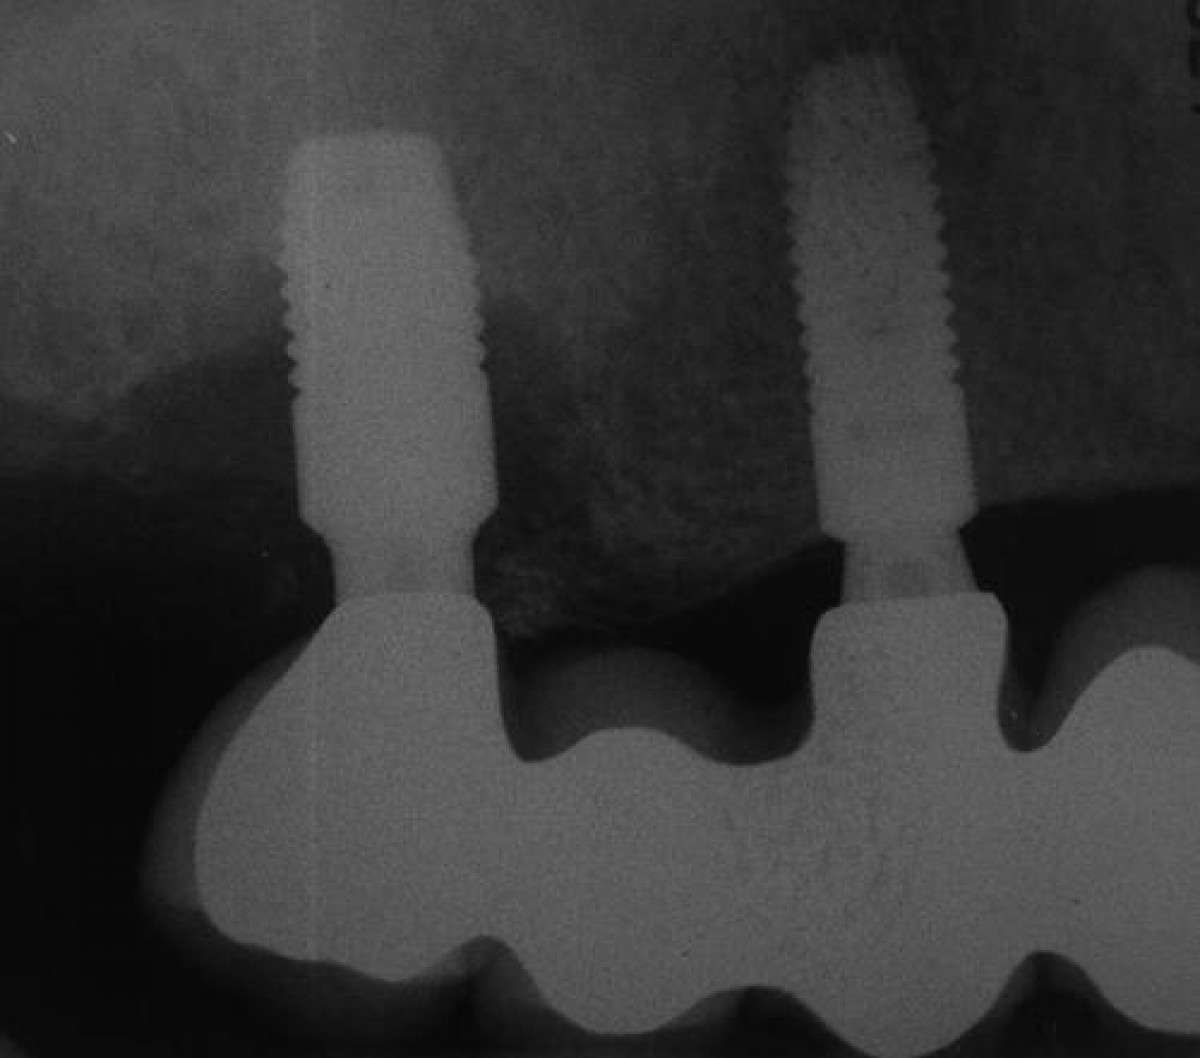

In a pilot clinical study, published on Journal of Periodontology, March 2021, the authors evaluated the additional benefits of Er: YAG laser irradiation in the regenerative surgical therapy of bone defects associated with peri-implantitis. Twenty-four patients with radiographic diagnosis of peri-implantitis and with an intraosseous defect were randomly assigned to one of two groups, test group and control group. Both the test group and the control group received the following treatment:

The only difference between the two groups was that the Er: YAG laser was also used in the test group to modulate and remove inflammatory tissue and to decontaminate the implant surface. Pocket depth (PD), clinical attachment level (CAL), and gingival index (GI) were clinically assessed by blinded examiners up to 6 months after surgery. Standardized radiographs were also taken to assess gain and filling of the bone defect. Student's t-tests were used to analyze clinical parameters.

Significant reductions in PD, GI, and CAL gain occurred over time in both groups. The test group demonstrated significantly higher PD reductions at the implant site than the control group (2.65 ± 2.14 versus 1.85 ± 1.71 mm; test versus control, P = 0.014). There were no statistical differences in CAL gain, GI reduction, radiographic linear bone gain, or proportional reduction in defect size. There was a positive trend for patients in the test group in narrow intrabony defects to PD reduction and CAL gain. Membrane exposure negatively compromised the overall treatment, the result of the CAL gain and the reduction of PD in the test group.